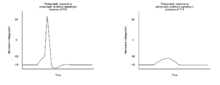

Tetrodotoxin (TTX) is a poison produced by organisms belonging to the Tetraodontiformes order, which includes the puffer fish, ocean sunfish, and porcupine fish.[50] Within the puffer fish, TTX is found in the liver, gonads, intestines, and skin.[6][51] TTX can be fatal if consumed, and has become a common form of poisoning in many countries. Common symptoms of TTX consumption include paraesthesia (often restricted to the mouth and limbs), muscle weakness, nausea, and vomiting[50] and often manifest within 30 minutes of ingestion.[52] The primary mechanism by which TTX is toxic is through the inhibition of sodium channel function, which reduces the functional capacity of neuron communication. This inhibition largely affects a susceptible subset of sodium channels known as TTX-sensitive (TTX-s), which also happens to be largely responsible for the sodium current that drives the depolarization phase of neuron action potentials.[6]

TTX-resistant (TTX-r) is another form of sodium channel which has limited sensitivity to TTX, and is largely found in small diameter axons such as those found in nociception neurons.[6] When a significant level of TTX is ingested, it will bind sodium channels on neurons and reduce their membrane permeability to sodium. This results in an increased effective threshold of required excitatory signals in order to induce an action potential in a postsynaptic neuron.[6] The effect of this increased signaling threshold is a reduced excitability of postsynaptic neurons, and subsequent loss of motor and sensory function which can result in paralysis and death. Though assisted ventilation may increase the chance of survival after TTX exposure, there is currently no antitoxin. The use of the acetylcholinesterase inhibitor Neostigmine or the muscarinic acetylcholine antagonist Atropine (which will inhibit parasympathetic activity), however, can increase sympathetic nerve activity enough to improve the chance of survival after TTX exposure.[50]